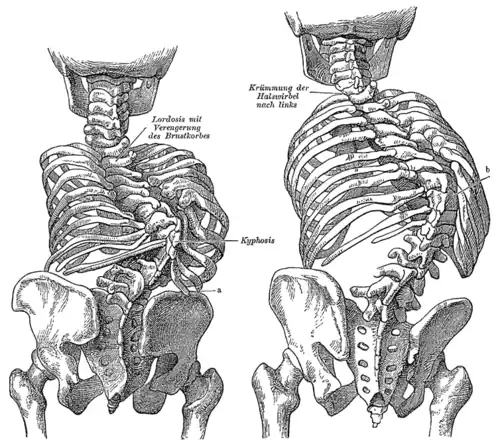

| Kyphosis (left) and scoliosis (right) depicting iliocostal contact (a) | |

Iliocostal friction syndrome, also known as costoiliac impingement syndrome, is a condition in which the costal margin comes in contact with the iliac crest. The condition presents as low back pain which may radiate to other surrounding areas as a result of irritated nerve, tendon, and muscle structures. It may occur unilaterally due to conditions such as scoliosis, or bilaterally due to conditions such as osteoporosis and hyperkyphosis.

Iliocostal friction syndrome can be a disabling painful condition that can affect the quality of life for individuals.[1] The predominant symptom is low back pain, which may radiate to the lower rib cage, flank, groin, buttock, and thigh.[2] Individuals may also experience intermittent aches along with a 'grating sensation' in the hip.[3] The pain may be aggravated by moving, twisting, bending, or by changing positions.[4] The condition may be bilateral as seen in individuals with hyperkyphosis or osteoporosis, but is more commonly unilateral as seen in individuals with scoliosis.[5]

Scoliosis has been known to cause unilateral iliocostal friction syndrome.[5] It is a condition in which the lateral curvature of the spine is measured to be more than 10 degrees. Scoliosis is typically categorized into congenital, neuromuscular, idiopathic, degenerative, and pathologic forms.[7] The decreased distance between the ribcage and the iliac crest can come in contact depending on the severity of the scoliosis curve.[8] There has also been reported instances where individuals experience iliocostal friction syndrome due to an abnormally long twelfth rib. This can be presented both bilaterally or unilaterally, depending on the individual.[3][8]

Another cause for bilateral iliocostal contact is based on the kyphosis curve of the spine. The thoracic spine is slightly curved due to the shape of the vertebral bodies and intervertebral discs, with a normal Cobb angle measurement between 20 and 40 degrees. Hyperkyphosis is a condition in which the curve of the kyphosis angle measures over 50 degrees. The kyphosis angle can be influenced by age, muscle tone,[12] vertebral fractures, and intervertebral degenerative disc disease.[13] Hyperkyphosis can result from posture, a congenital deformity, heritable conditions such as Scheuermann's disease,[14] tumours, trauma, neuro-muscular disease, postlaminectomy syndrome, dwarfism, and infections such as tuberculosis which can result in Pott's disease.[15] The curvature of hyperkyphosis may result in a decrease of space between the ribs and the iliac crest, causing iliocostal friction syndrome.[11]